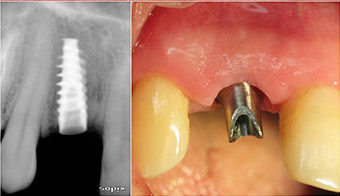

Coroas sobre Implantes

Com as técnicas utilizadas conseguimos um aspecto natural mesmo em coroas sobre implantes.

Coroa procera sobre implante no canino

Coroa procera sobre coto em titânio

Coroa em cerâmica pura sobre coto em titânio